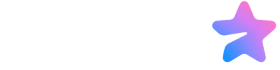

درک عملکرد قلب

قبل از بررسی نشانهها، خوب است درک پایهای از نحوه پمپاژ خون توسط قلب داشته باشیم. قلب را بهعنوان یک پمپ چهارحفرهای تصور کنید. خون از بدن به دهلیز راست بازمیگردد، سپس به بطن راست میرود که آن را به ریهها پمپ میکند تا اکسیژن دریافت کند. پس از آن، خون غنی از اکسیژن به دهلیز چپ و سپس به بطن چپ میرسد. بطن چپ بخش قدرتمند قلب است؛ این بخش خون را به سراسر بدن پمپ میکند. این سیستم، اگر عضله قلب ضعیف شود، اگر مقاومت زیادی وجود داشته باشد (مانند فشار خون بالا)، یا اگر دریچهها درست کار نکنند، میتواند ناکارآمد شود. وقتی قلب نتواند خون را بهطور مؤثر پمپ کند، مایعات میتوانند تجمع پیدا کنند و علائم مختلفی ایجاد کنند.